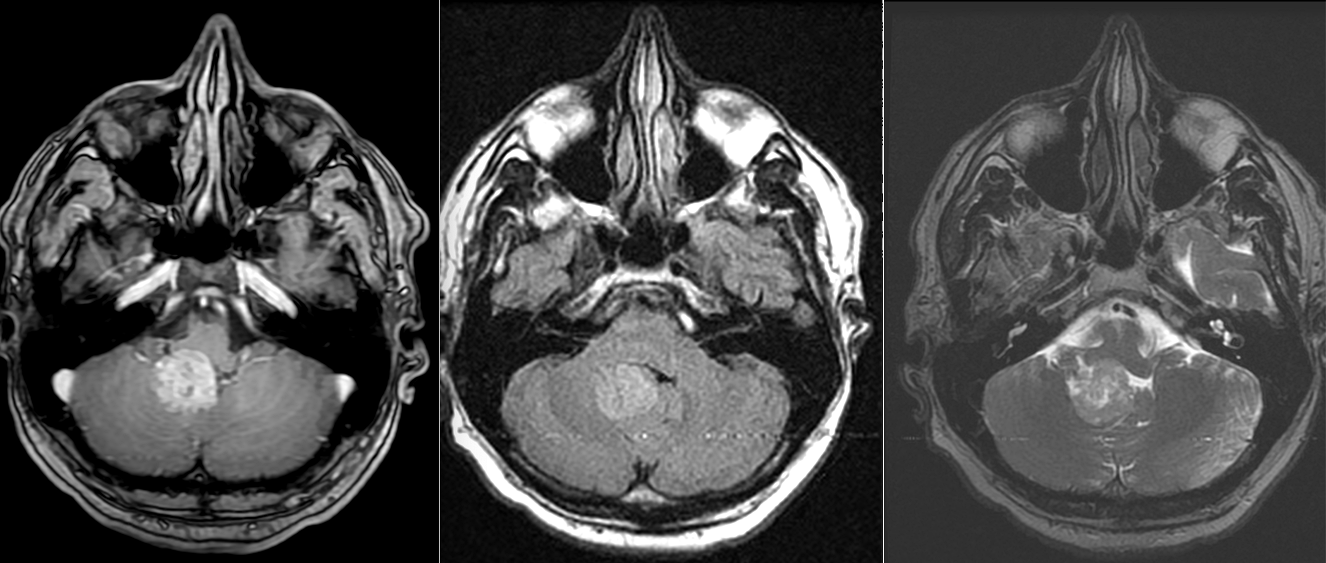

RMN cerebral și/sau spinal cu gadolinium este standardul de aur. Tumorile apar ca mase bine delimitate, care pot conține chisturi și zone de necroză. Adesea pot conține microcalcificări (vizibile mai bine pe CT). Datorită localizării intraventriculare, ependimoamele pot determina obstrucția circulației lichidului cefalo-rahidian și hidrocefalie.

Pentru pacienții care nu pot efectua RMN, tomografia computerizata (CT) este utilă, dar tumorile de mici dimensiuni pot trece neobservate.

Diagnostic diferențial

Ependimoamele trebuie diferențiate de alte tumori cu localizare ventriculară sau în fosa posterioară:

Meduloblastom

Astrocitom pilocitic

Metastaze

Tumori neuroectodermale primitive

Papilom de plex coroid

Diagnosticul diferențial se face pe baza imagisticii, histologiei și, tot mai important, pe profilul molecular.